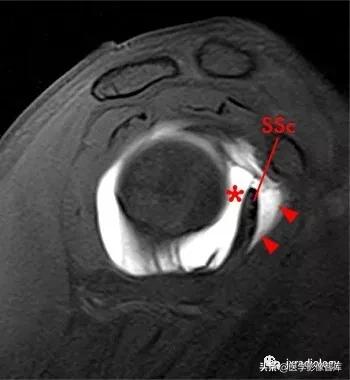

图2: 肩胛下肌上隐窝 (滑囊)( superior subscapularis recess)和

喙突下滑囊(subcoracoid bursa)

SSR(superior subscapularis recess):肩胛下肌上隐窝;

subcoracoid bursa:喙突下滑囊

星号:superior subscapularis recess:肩胛下肌上隐窝

箭头:subcoracoid bursa:喙突下滑囊

SSc:肩胛下肌腱